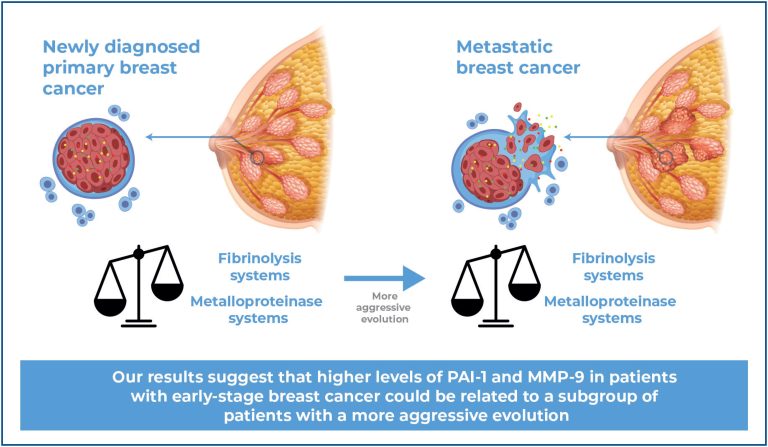

A cross-sectional study on the expression of fibrinolytic system components and metalloproteinase-9 in women with early-stage and metastases breast cancer in Tucumán, Argentina

einstein (São Paulo). 07/Apr/2025;23:eAO1237.

View Article07/Apr/2025

A cross-sectional study on the expression of fibrinolytic system components and metalloproteinase-9 in women with early-stage and metastases breast cancer in Tucumán, Argentina

DOI: 10.31744/einstein_journal/2025AO1237

Highlights ■ No clinically significant differences were observed in platelet counts or global coagulation test results. ■ t-PA values decreased in patients with metastases. ■ PAI-1, DD, and MMP-9 levels increased in patients with metastases. ■ High levels of PAI-1 and MMP-9 in the early stages could indicate an aggressive course in patients. ABSTRACT Objective: The hemostatic and matrix metalloproteinase (MMP) systems are known to be altered in patients with breast cancer. This cross-sectional study aimed to explore the fibrinolysis […]

Keywords: Breast disease; Breast neoplasms; Fibrinolysis; Matrix metalloproteinase; Metastasis neoplasms; Plasminogen activator inhibitor 1; Standard coagulation tests